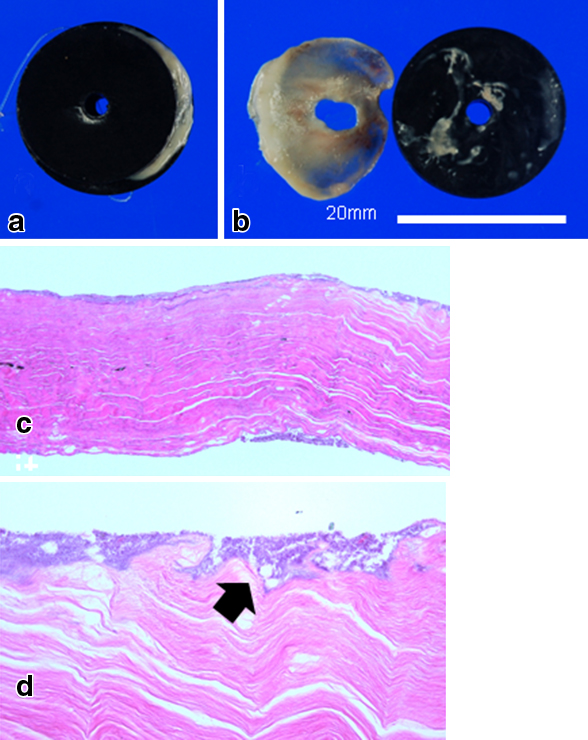

施術後5日目では圧迫磁石にずれはなく(Fig. 4a, b),8日目に肛門から圧迫磁石の脱落があり,閉塞部組織は両磁石に圧迫壊死した形で排出され,使用した磁石と同直径の開通を得た(Fig. 4c, d).再狭窄を防ぐために,再開通部が安定するまでは,外来で2週間毎に3か月間,硬性ブジーによる拡張を行った.二つの磁石に圧着されて脱落した閉塞部組織は,直腸の線維組織として矛盾なく,悪性所見はなかった(Fig. 5).

Eight days after the Yamanouchi method. a) The two magnets squeezing the occlusion area dropped out from the anus. b) The tissue of the occlusion and magnets were the same size. c) Histologically, the mucosal epithelium is completely exfoliated. Scattered foreign bodies containing bacteria is found on the surface (arrow). Strong fibrosis is observed in the stroma without vascular structure (HE c: 4× d: 20×).